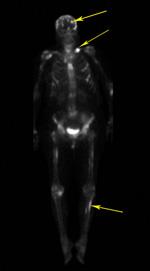

For example, the metastatic breast cancer project allows people with metastatic breast cancer to enroll themselves. Osteolytic metastases are more common than osteoblastic metastases. Bone metastasis can cause pain and broken bones.

For example, the metastatic breast cancer project allows people with metastatic breast cancer to enroll themselves. When metastatic breast cancer spreads to the bones, it's called bone metastases. Bone is one of the most common places for breast cancer to spread. Bone metastases are not bone cancers.